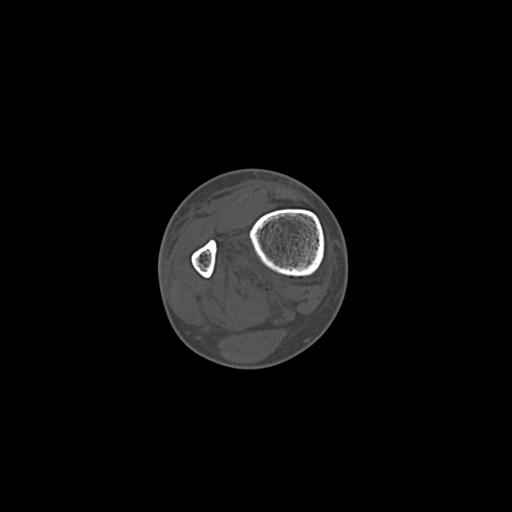

49554 3/13 膝 4R 3/16 4R 1/18 2R 78歳男性 膝蓋骨骨折

100612 11/25 1/20 右膝 2R 84歳女性 右TKA

91983 11/16 左膝 2R 11/18 2R 55歳男性 脛骨骨切り術